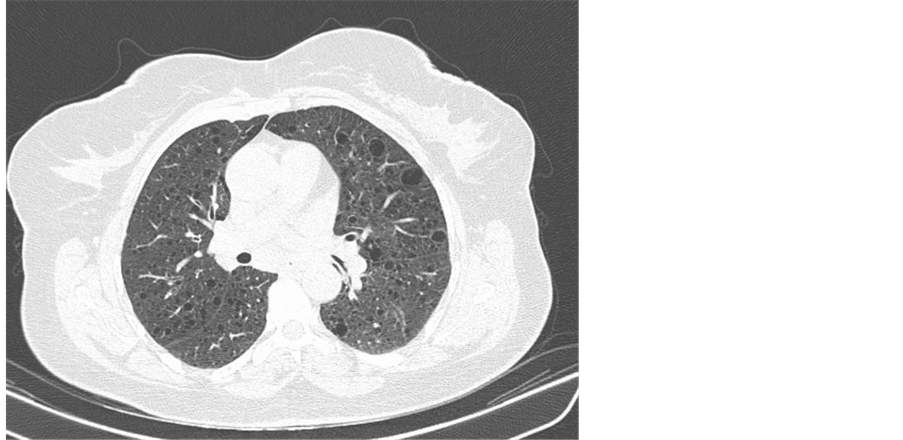

Despite becoming apyretic, shortness of breath, cough and hypoxaemia persisted and the patient was submitted to a pulmonary angiogram ct which revealed numerous thin-walled air cysts affecting upper and medial zones of both lungs (Figure 1), typical images of pulmonary lymphangioleiomyomatosis (Figure 2) [6] .

Figure 2. Axial cut from medial zone parenchyma typical of pulmonary lymphangioleiomyomatosis.